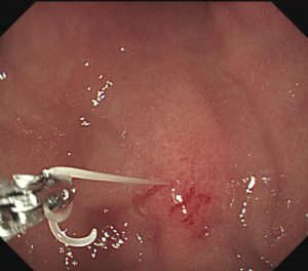

によると2016年には124件の患者が確認されています。アニサキスとは長さが23cmの白色の少し太い糸のような寄生虫で、サバ、イワシ、カツオ、サケ、イカ、サンマ、アジ、ホッケなどに寄生しています。寄生した魚介類を生で食べると、食後34時間後に突然、腹部の激痛、吐き気・嘔吐が襲います。まれに半日以上から、長い時は1週間くらいたって症状が出ることもあり、この時は胃ではなく小腸まで虫が侵入していると考えられます。 一部の人には、じんま疹のような発疹やかゆみが現れることがあり、アニサキスに対するアレルギー反応だと考えられています。アニサキスは胃アニサキス症が圧倒的に多く、腸アニサキス症は48%と少なめです。胃アニサキス症は胃カメラでアニサキスを摘出するのが一番の治療法です。鉗子で胃壁から虫をつまみ出した瞬間、嘘のように痛みが消えます。私はこれまで23例しか当たったことがありませんが、なかなか印象的です。腸アニサキス症の場合は痛み止めや吐き気止め、抗生剤、ステロイド、抗アレルギー薬などの対症療法を行います。通常アニサキスは人体中では1週間程度で死んでしまいます。しかし中にはアニサキスが腸閉塞や腸穿孔を起こすことがあり、開腹手術が必要となるケースもあります。